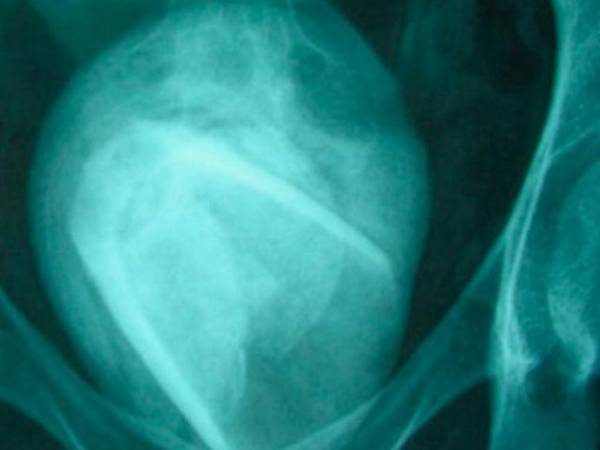

Un ultrasonido reveló lo que la fémina tenía en el interior de su vejiga.

Túnez

Hallan un vaso de vidrio en la vejiga de una mujer

La mujer acudió al hospital quejándose de fuertes dolores debido a una infección urinaria